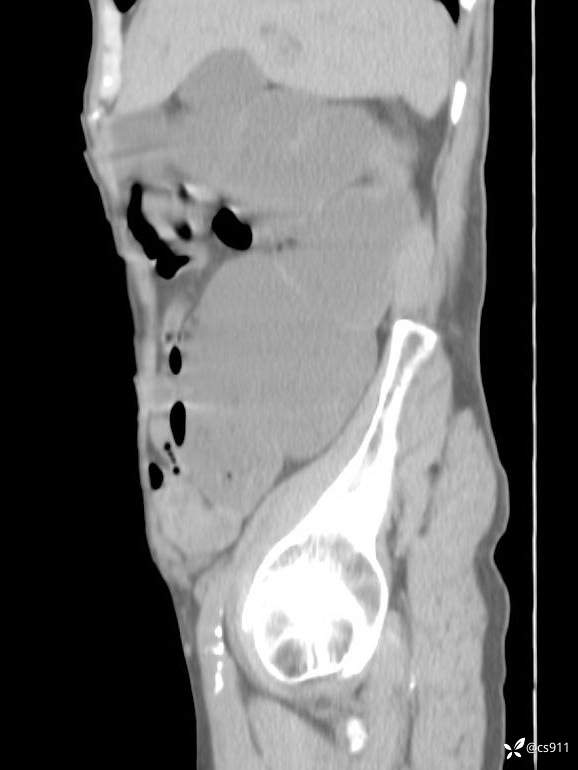

急腹症之急诊CT,原因?答案公布

男,77岁,腹痛、腹胀伴恶心呕吐1天。呕吐胃内容物,非喷射性呕吐,有咖啡色样胃内容物,诉有胃穿孔病史。查体:全腹平,下腹部压痛,全腹无反跳痛,叩诊呈浊音,移动性浊音阴性,肠鸣音减弱,1-2次/分。肛检:直肠未扪及明显肿物,可触及大量粪块。

T 36.6℃ P 80次/分 R 26次/分 BP 100/60mmHg

白细胞(WBC) H 14.55 10e9/L 4-10

中性粒细胞百分率(NEUT%) H 85.7 % 40-75

血淀粉酶(AMY) HH 1859 U/L 35-135

癌胚抗原(CEA) H 27.44 ng/ml 0-5

呕吐物 潜血试验 * 阳性 阴性

患者轮椅入室检查神志清楚, 能配合摆位和呼吸